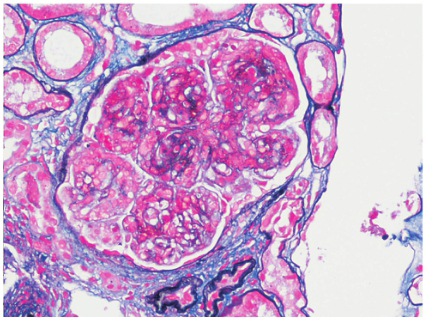

肾活检示免疫荧光:C3(+++),余阴性,系膜区、毛细血管壁颗粒样沉积(图1)。光镜下可见24个肾小球,肾小球系膜细胞和基质中重度弥漫增生,广泛插入,基底膜增厚,双轨征形成,系膜区、内皮下嗜复红蛋白沉积;肾小管上皮空泡及颗粒变性,灶状萎缩;肾间质灶状淋巴和单核细胞浸润伴纤维化;小动脉管壁增厚;符合膜增生性肾小球肾炎(MPGN)(图2)。电镜下肾小球系膜细胞和基质中度增生,广泛插入,基底膜增厚,上皮下、基底膜内、内皮下、系膜区均可见电子致密物沉积,上皮足突广泛融合(图3);符合MPGN。结合患者免疫荧光结果,最终诊断为C3肾小球肾炎。

图2 MPGN型C3肾小球肾炎:肾小球系膜细胞增生和系膜基质增多,

毛细血管壁增厚,双轨征形成(PASM+Masson×200)